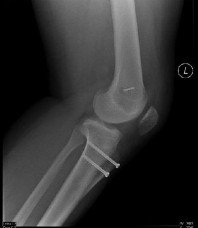

Question 14:

A 23-year-old collegiate basketball player sustains a fracture of the fifth metatarsal at the metaphyseal-diaphyseal junction (Jones fracture). He demands the quickest safe return to play. What is the current standard of care for a competitive athlete with an acute Jones fracture?

Options:

- Non-weight bearing short leg cast for 6 weeks

- Weight-bearing in a stiff-soled boot for 4 weeks

- Percutaneous intramedullary screw fixation

- Open reduction internal fixation with a lateral neutralization plate

- Excision of the proximal fragment and peroneus brevis advancement

Correct Answer: Percutaneous intramedullary screw fixation

Explanation:

Acute Jones fractures (Zone II) in high-level competitive athletes are best treated with intramedullary screw fixation. This approach significantly decreases the time to clinical and radiographic union, decreases the nonunion rate, and allows for a much earlier return to play compared to conservative management.